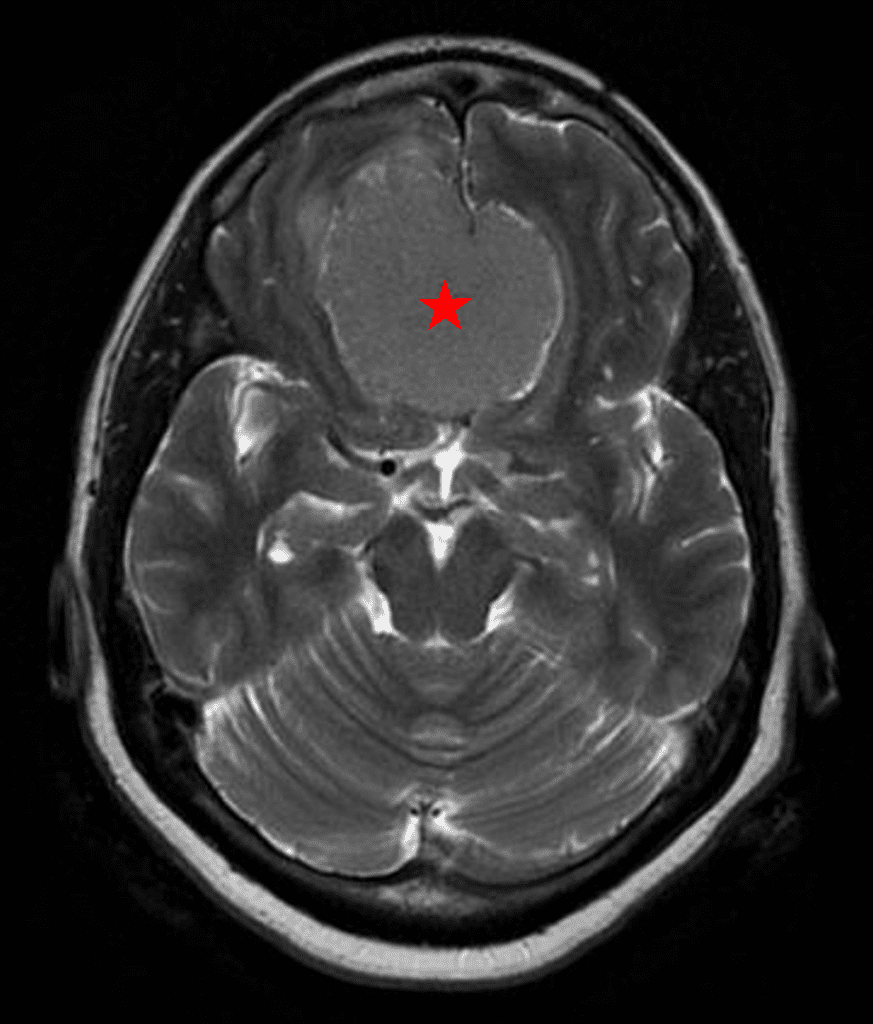

She was started on high-dose steroid and antiseizure prophylactic medicine. Surgical intervention was offered for mass effect, symptomatic relief, neurologic preservation, and histopathologic diagnosis. Dr. Gaudin performed a bifrontal craniotomy with complete resection of neoplasm through an interhemispheric and subfrontal approach. Postoperative imaging demonstrated a gross total resection without residual tumor and resolution of mass effect (Figure 1b and 2b). Intraoperative pathology was consistent with meningioma, WHO grade 1. She recovered very well, and was discharged home on postoperative day 3. On her follow-up outpatient visit, her preoperative symptoms had fully resolved, and her olfactory sense was maintained.

Figure 2a – Preoperative MRI demonstrating an extra-axial lesion with surrounding vasogenic edema and mass effect on the frontal lobes.